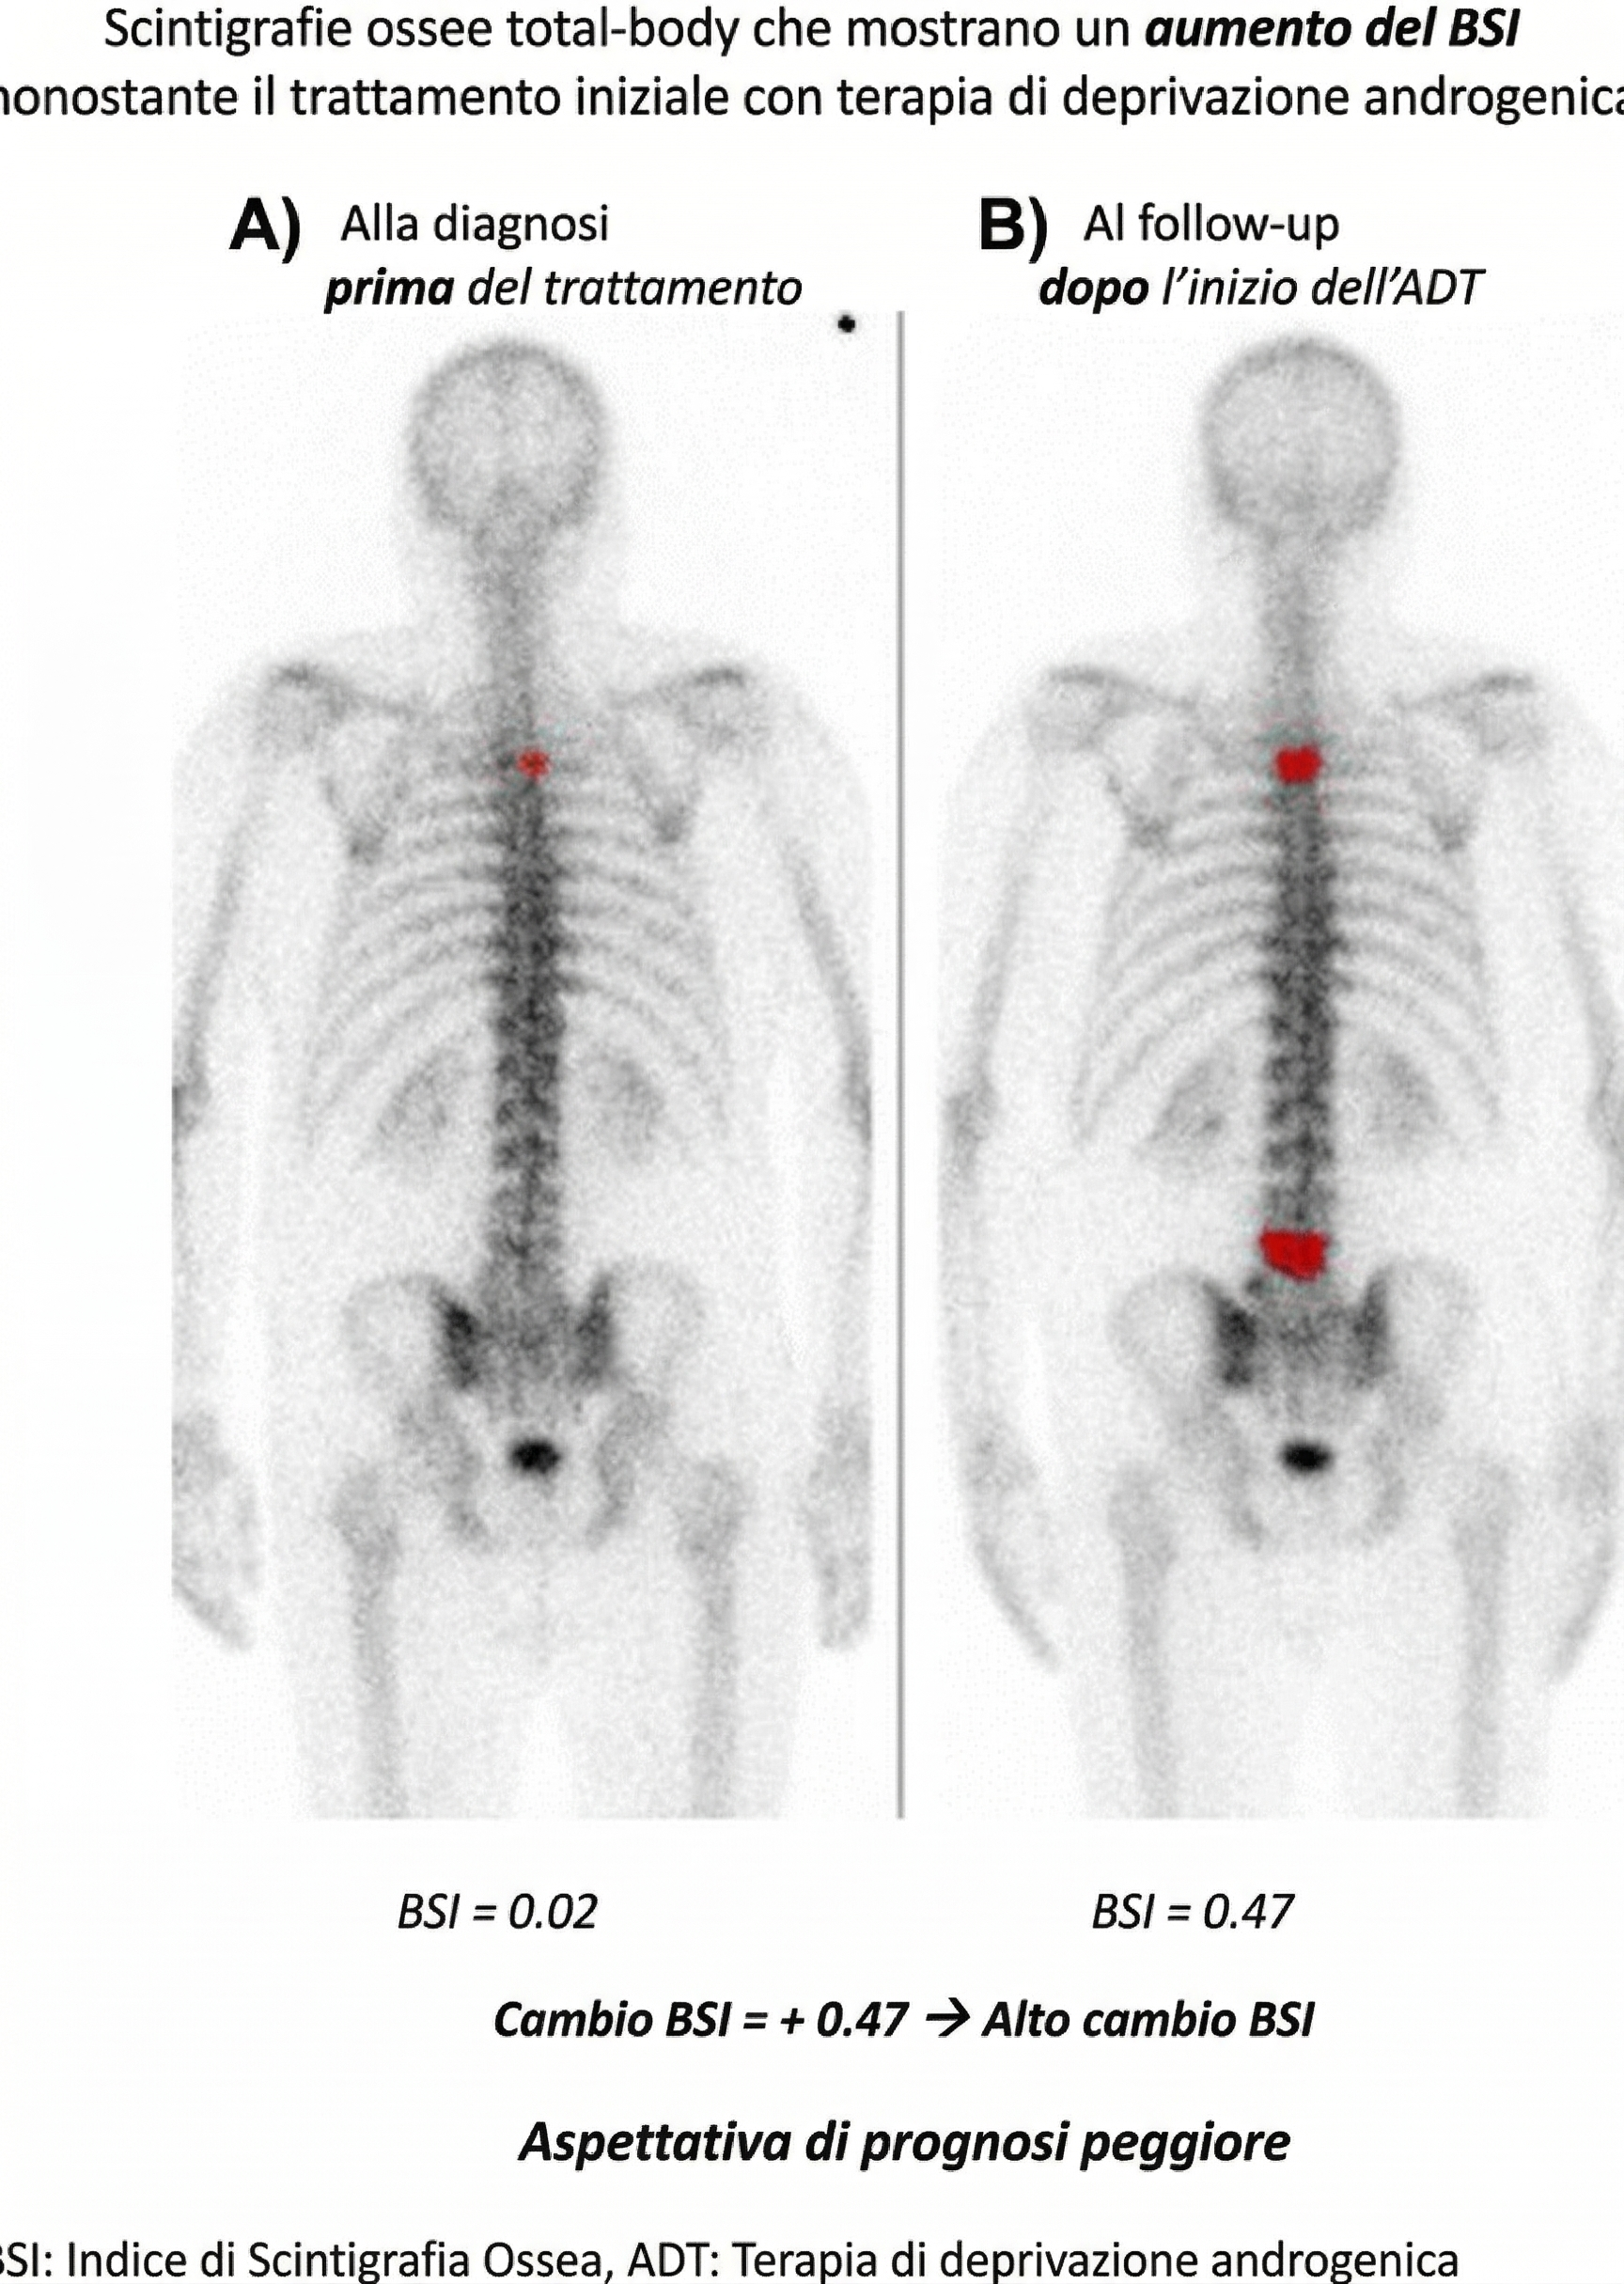

Bone Scan Index (BSI): calcolato tramite software automatizzati, il BSI esprime il carico tumorale come percentuale della massa scheletrica totale. Un BSI elevato alla diagnosi correla con una ridotta sopravvivenza globale nel cancro alla prostata;1213

Bone Scan Index

A) Il BSI valuta l’estensione della captazione patologica in ogni singolo segmento osseo in rapporto a un modello anatomico standard (“reference man“). La somma di questi valori fornisce l’indice globale. Le metastasi del carcinoma prostatico si localizzano tipicamente nelle aree ricche di midollo rosso attivo, che costituiscono circa il 40% dell’intera massa scheletrica. Il BSI offre un dato numerico oggettivo per monitorare nel tempo l’andamento clinico. B) La percentuale di massa scheletrica totale coinvolta dal tracciante progredisce dallo 0%, allo 0,59%, al 7,7% e, a seguito del trattamento, scende al 5,4%.

Il Bone Scan Index viene utilizzato per quantificare visivamente (in rosso) e numericamente il carico tumorale (tumor burden) a livello scheletrico, confrontando l’esame basale con quello di follow-up.

Le immagini documentano un evidente aumento delle lesioni metastatiche nel tempo. Questo si traduce in un marcato incremento del valore del BSI nonostante l’approccio terapeutico (deprivazione androgenica).

L’analisi quantitativa conferma che un “delta” (variazione) elevato del BSI in aumento è un marker sfavorevole, strettamente correlato a una prognosi peggiore e a una ridotta sopravvivenza globale.